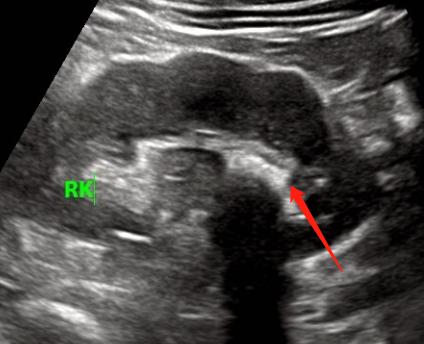

肾结石一般躲在我们的肾窦的各个角落内。

看,上面那个结石就已经走到输尿管了。

此时因为较大,堵住了输尿管,导致肾脏内的尿液排不出去,所以就会腰疼。